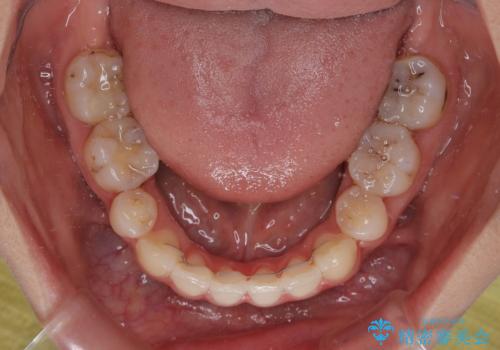

口元の突出感が認められ、更には左右で異なる咬合状態であったため、下顎右側は第二小臼歯を、左側は第一小臼歯を抜去することでバランスを取るような治療計画としました。

また上顎前歯は大臼歯に補綴治療が必要であったため、矯正治療後にオールセラミッククラウンによる補綴治療を行うこととしました。

下顎の抜歯位置を左右で変えることで、最終的に上下正中をほぼ一致させることができました。